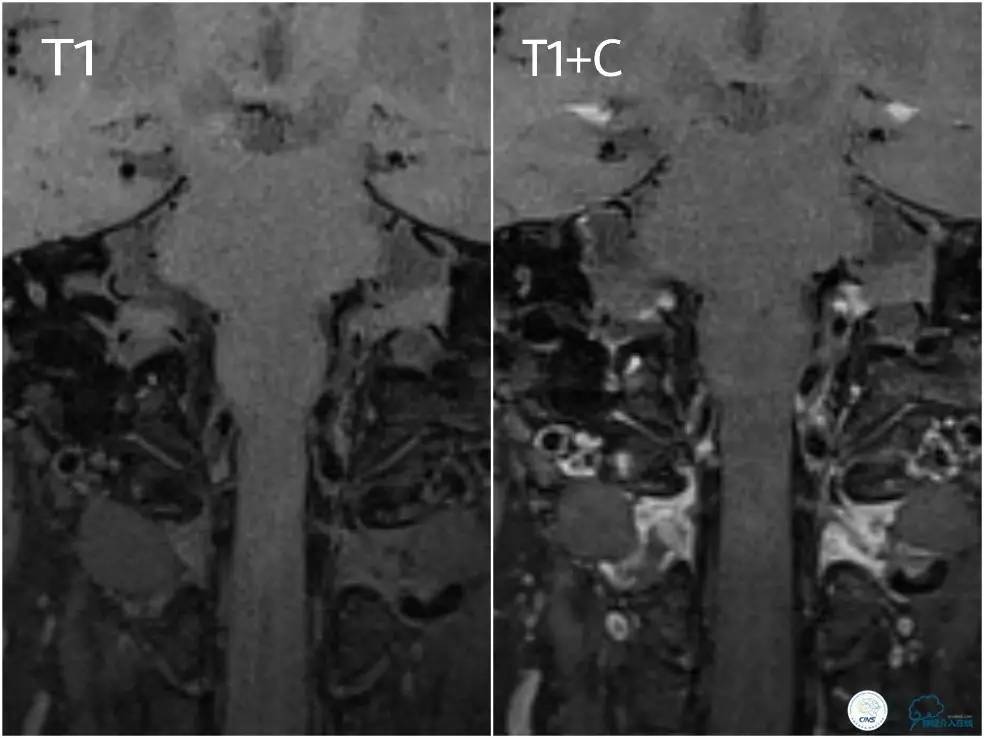

高分辨核磁(图2):左椎动脉后外侧管壁不规则增厚,增强局部可见不规则强化,局部管腔不规则狭窄。考虑左侧椎动脉管壁斑块形成,管腔局部狭窄。

图2